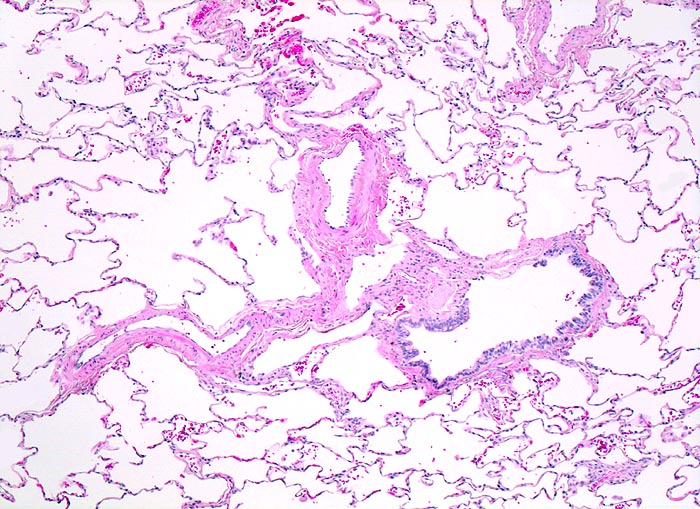

PathoPic ID 4363 - normales Lungenparenchym

normales Lungenparenchym

Lunge

Die Alveolarsepten sind sehr schlank. Die

Lungenarterienäste verlaufen zusammen mit den Luftwegen. Im Bild ein

Bronchiolus.

Histologie

50